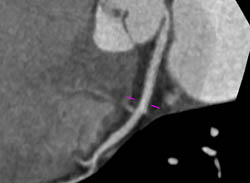

Diagnosis

LAD Disease